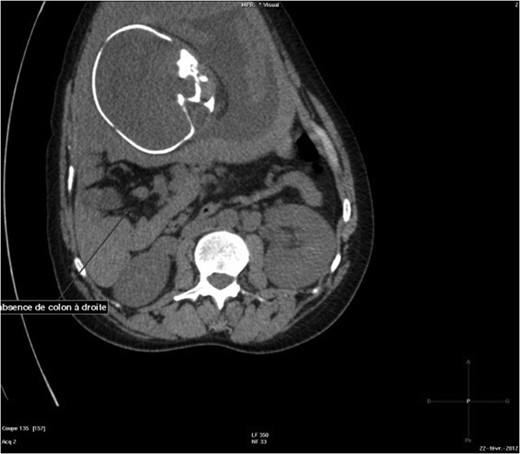

The abdominal-pelvic CT-scan showed a pre-splenic left position of the caecum and right colon, with no part of the colon on the right. The radiologist concluded that the patient was suffering from a complication of intestinal malrotation (IM) (Figs 1, 2, 3).

Abdominal-pelvic CT-scan, non-contrast enhanced, in the sagittal plane.